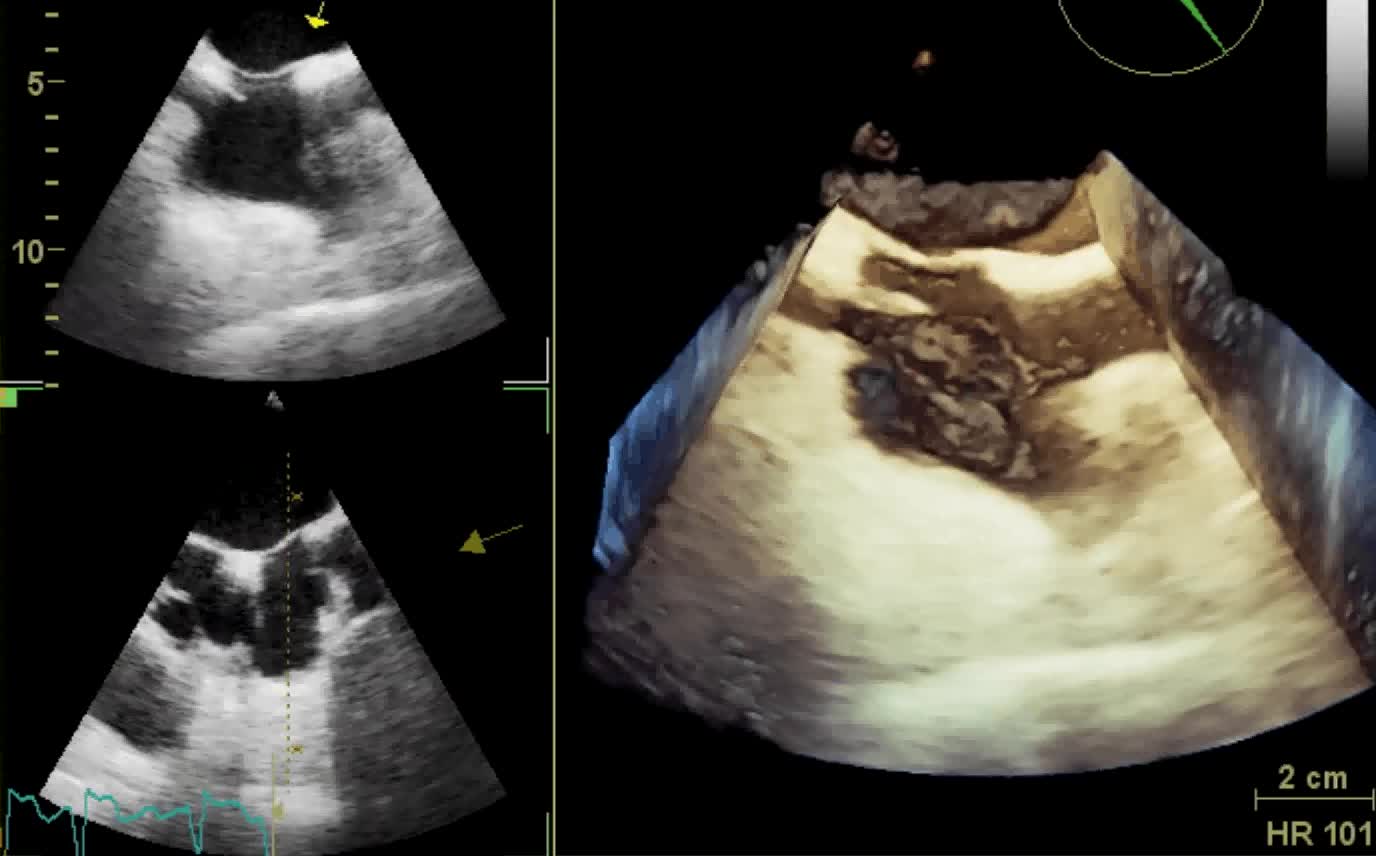

Il ruolo clinico dell’ecocardiografia in 4D

Autore:

Francesco Faletra